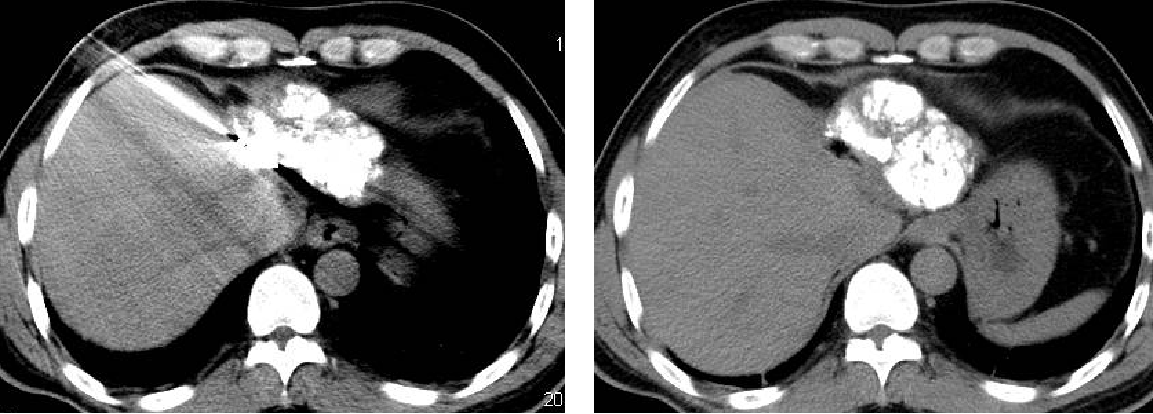

2011-02-12复查CT示:肝左叶碘油散在沉积,病灶大部分仍有活性,肝右后叶病灶未见碘油沉积;门静脉癌栓较前进展,累及主干及右支;肝左静脉及下腔静脉内癌栓无明显变化。AFP:26802 ng/ml。

2011-04-20复查CT示:肝左叶病灶较前缩小,肝右叶病灶见碘油致密沉积;门脉癌栓左支较前缩小,右支癌栓消失;下腔静脉、肝左静脉癌栓消失。AFP:4983 ng/ml。

2011-06-09(第二次TACE后4个月)复查肝脏CT示:肝左叶病灶继续缩小,但仍有肿瘤残留。AFP:8137 ng/ml(较上次复查明显升高)。

2011-08-15复查CT示:肝左叶病灶大小较前相仿,仍有肿瘤残留。